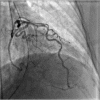

Takotsubo cardiomyopathy

Keywords: Apical ballooning syndrome; broken heart syndrome; cardiomyopathies; female; magnetic resonance imaging; sex factors; stress cardiomyopathy; takotsubo cardiomyopathy/diagnosis/drug therapy/epidemiology/etiology/physiology/physiopathology/psychology/surgery/therapy; ventricular dysfunction, left.